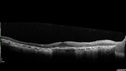

Concentric Geographic Atrophy - 76 year old man385 viewsGradual vision loss, worse at night. VA 20/40 OU.     (0 votes)

76 year old man The patient has noticed that his vision is getting worse at night. The vision loss has come on gradually. He notices that his vision in low lighting is poor and at night with oncoming headlights.

VA OD: Dcc20/40-1 NscJ7

VA OS: Dcc20/40-1 NscJ7

IOP: TP: OD:17 OS:18 Time:12:01 PM